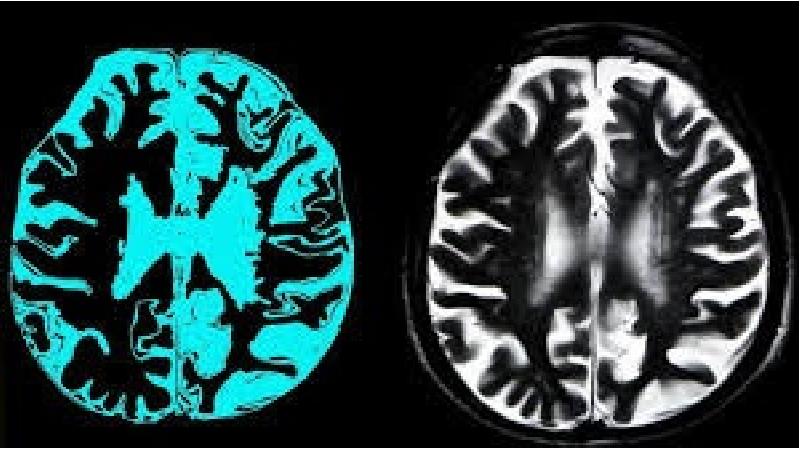

زوال عقل ناشی از آسیب به سلولهای مغزی است. آسیب به سلولهای مغزی باعث کاهش توانایی ارتباطی سلولهای مغز میشود. هنگامی که سلولهای مغز قادر به برقراری ارتباط طبیعی نیستند، تفکر، رفتار و احساسات تحت تأثیر قرار میگیرد.